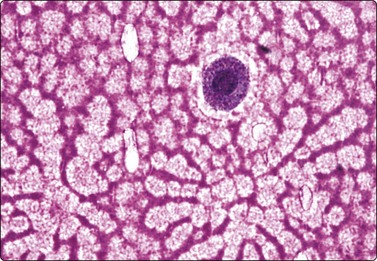

Merkel cell carcinoma (neuroendocrine carcinoma of skin) (Fig. 14.17, and see Fig. 5.23)61,62

image

Fig. 14.17 Merkel cell carcinoma

(A) Poorly cohesive cells; nuclear pleomorphism and some molding, scanty blue cytoplasm resembling lymphoid cells (MGG, HP); (B) Cellular smear of dispersed small cells with round, dark nuclei (Pap, HP); (C) Dot-like positive staining with CAM5.2 (immunostaining, HP).

Primary neuroendocrine carcinoma of skin is an uncommon neoplasm, mainly seen in elderly patients and most often in the head and neck. It is locally aggressive and often metastasizes to regional lymph nodes. Clinically and cytologically, Merkel cell tumor can be difficult to distinguish from non-Hodgkin lymphoma when it presents as lymphadenopathy without an obvious primary, as is often the case (see Chapter 5).

Page 379

Smears are usually highly cellular. The cells are mainly dispersed but some are clustered or form single files with nuclear molding and sometimes rosette-like groups. The main differential diagnoses are lymphoma and metastatic small cell carcinoma. Amelanotic melanoma may also be considered. The absence of lymphoid globules in the background and subtle differences in nuclear chromatin help in this distinction. Staining for CAM5.2, CK7 and CK20 demonstrates characteristic dot-like intracytoplasmic deposits in the tumor cells (Fig. 14.17C), and staining for neuroendocrine markers is usually positive. Electron microscopy shows well-demarcated whorls of cytoplasmic filaments.